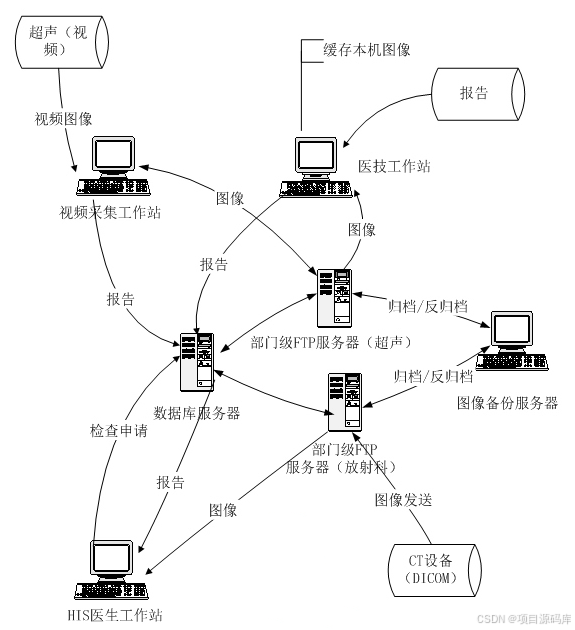

PACS系统即医学影像存档与通信系统,是医疗领域中不可或缺的信息技术系统。它主要负责医院内医学影像的数字化存储、管理、传输和显示,极大地促进了医疗影像信息的高效利用和共享。它可以集成多种医疗设备,如 CT、MR、CR、超声、视频采集、X 光机、 心血管机、核医学等,将这些设备产生的数字影像转换成标准格式,进行存储和管理,以便医生和专业技术人员进行诊断和治疗。

业务流程与系统集成

PACS系统与HIS(医院信息系统)和RIS(放射信息系统)紧密集成,业务流程大致如下:

1. 临床医生通过HIS系统开具电子检查单。

2. RIS系统进行预约、审核和费用确认。

3. PACS与RIS通过HL7消息交换信息,调度检查。

4. 检查完成后,影像以DICOM格式发送到PACS系统。

5. 影像经过质量控制后存储,并可被授权用户快速调阅。

PACS影像工作站:

RIS分诊登记工作站

解决病人就诊时排队的无序、医生工作量的不平衡、环境的嘈杂等问题,将病人分流到各个科室;分诊工作站还提供与HIS对接接口、排队管理、分诊信息大屏幕显示等功能。

超声工作站:

内镜工作站: